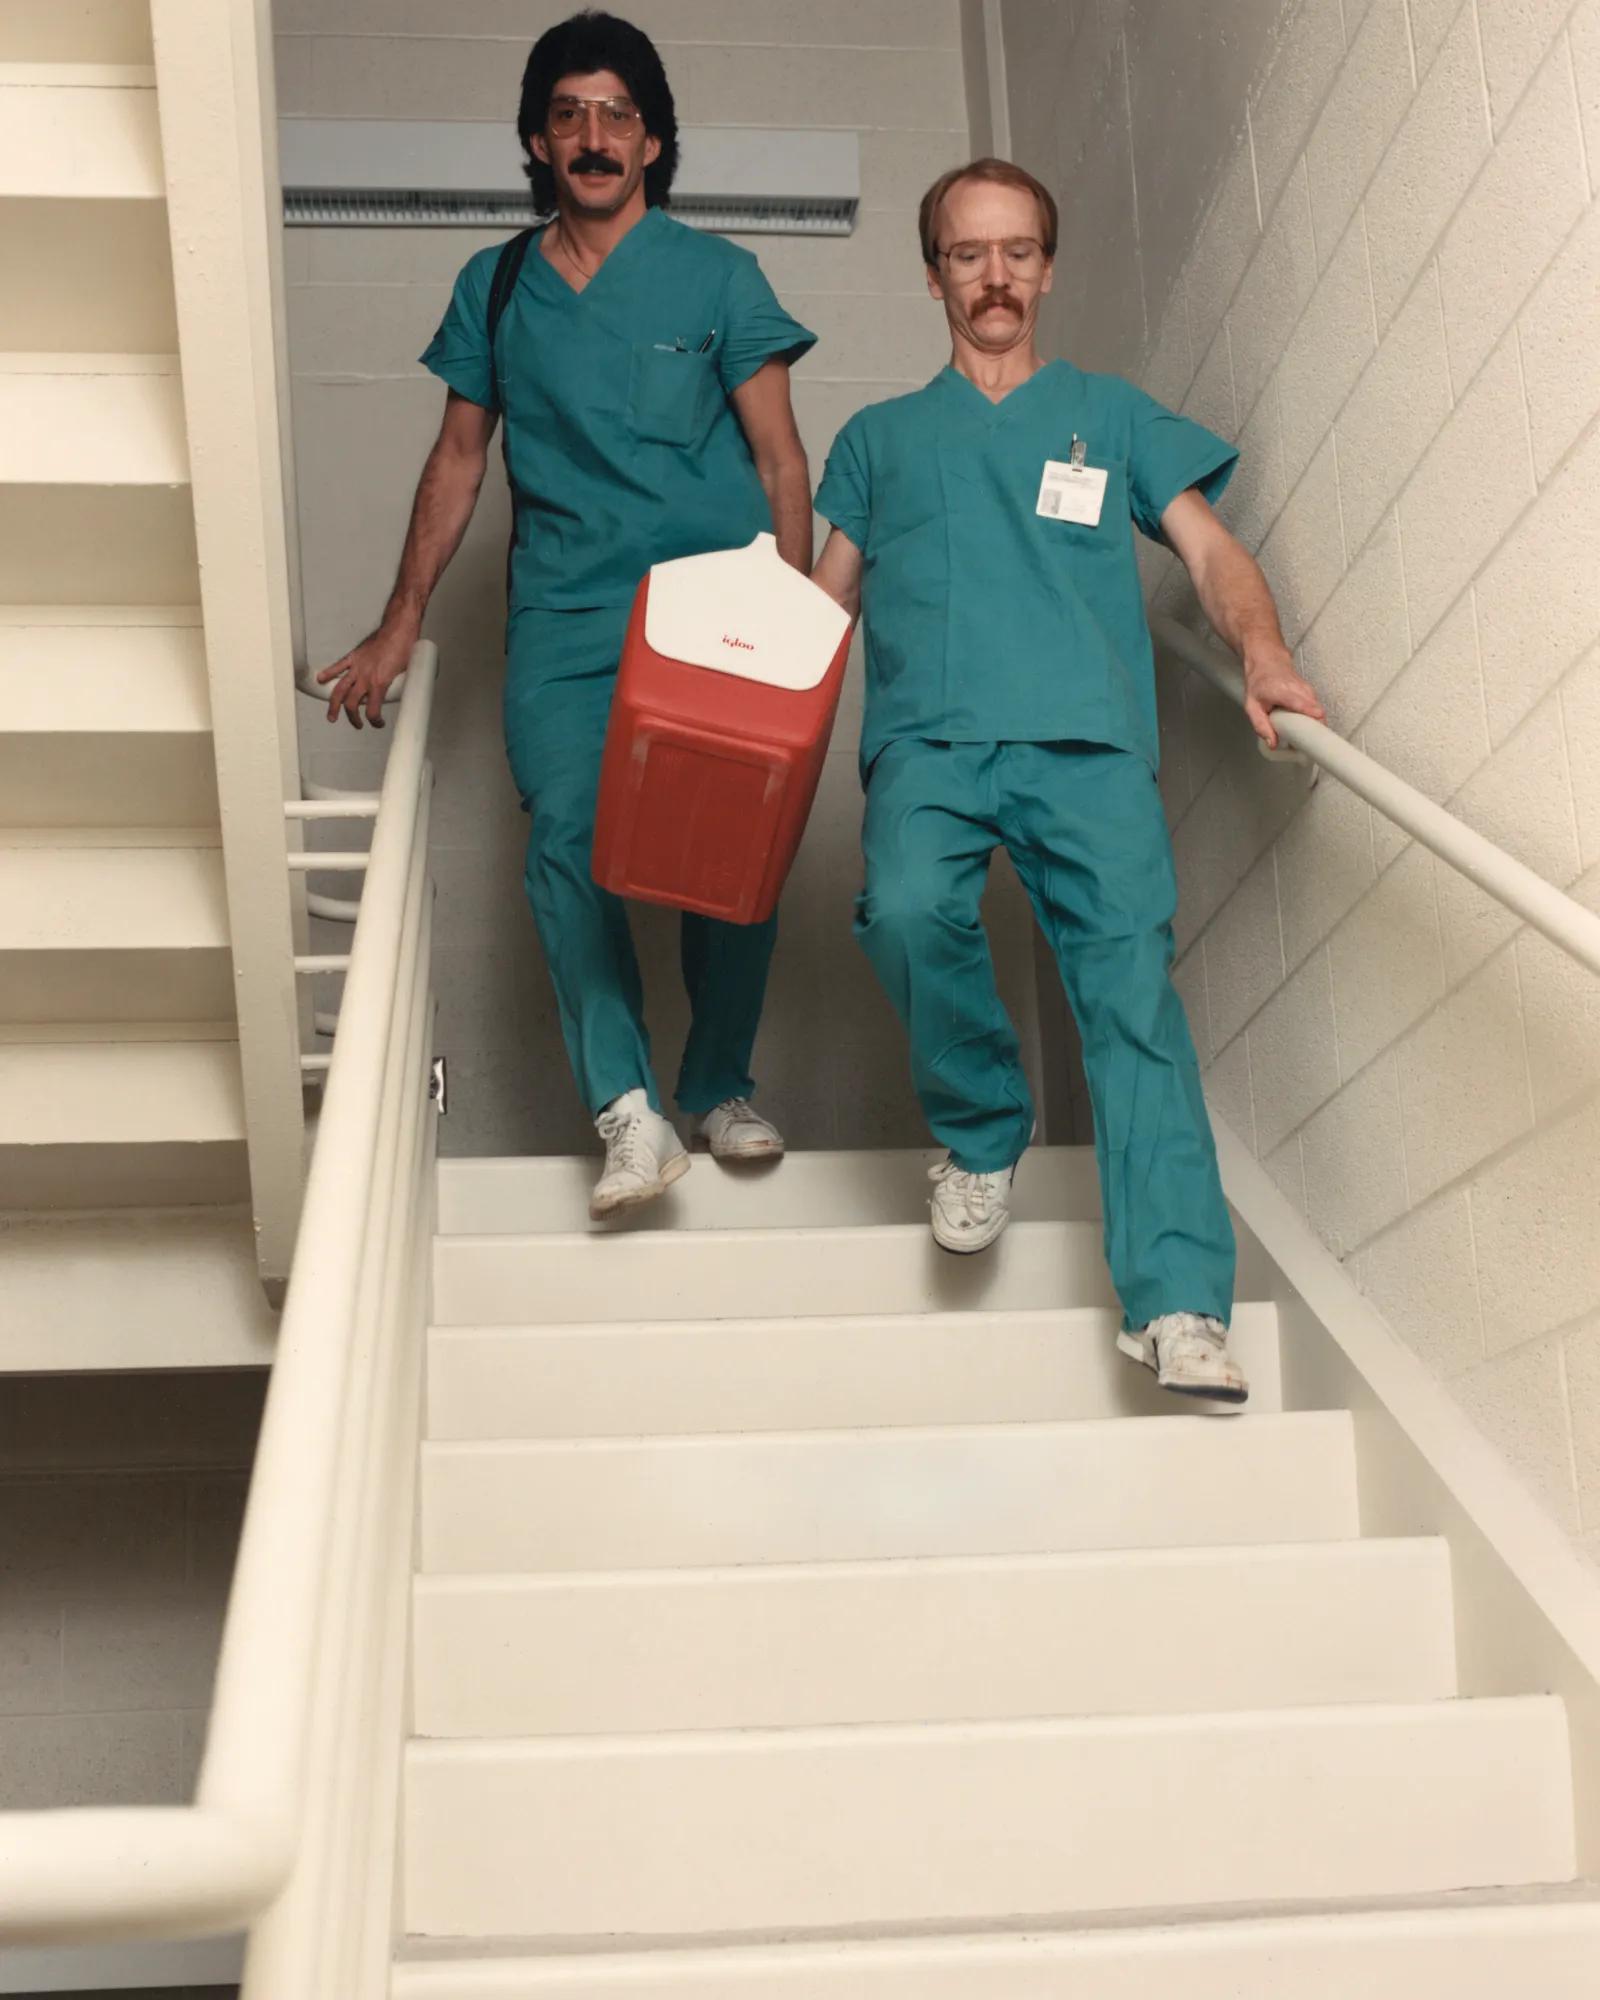

The 1980s was a decade in which Cleveland Clinic’s growing reputation drove expansion of the facility from 17 buildings on 62 acres to 30 buildings on 100 acres. With 9,134 employees, Cleveland Clinic became the city’s largest private employer in 1988. Also notable in the 1980s is the establishment of Cleveland Clinic’s organ transplant programs and its landmark 100,000th cardiac catheterization in March 1984. Cleveland Clinic pioneered healthcare marketing in the 1980s. It was one of the first hospitals to advertise and to issue colored scrubs in Cleveland Clinic blue.

The heart transplant program is established in 1984. In 1998, a record-breaking year for the program, 113 patients were transplanted, including eight pediatric patients.